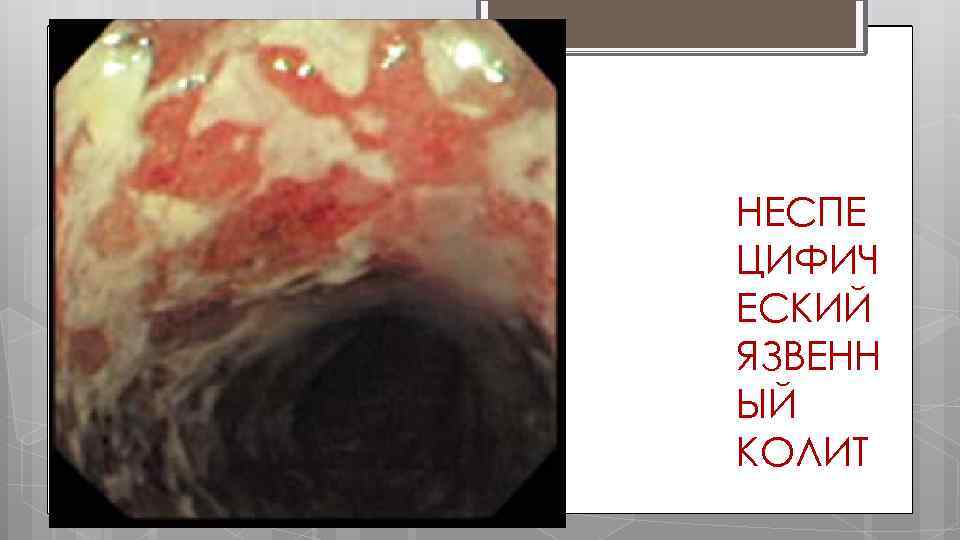

ЭНДОСКОПИЧЕСКИЕ ПРИЗНАКИ Отек, гиперемия слизистой, появление грануляций на ее поверхности, отсутствие сосудистого рисунка. Слизистая оболочка легко ранимая, кровоточит. Язвы на фоне виспалительно измененной слизистой оболочки покрыты фибрином, гнойным экссудатом.

НЕСПЕ ЦИФИЧ ЕСКИЙ ЯЗВЕНН ЫЙ КОЛИТ